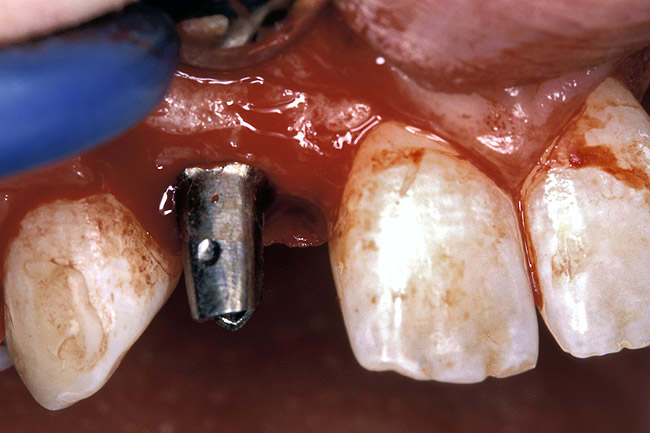

Before the day of surgery, the patient was seen by the orthodontist for the removal of the orthodontic brackets. The patient still was not pleased with the position of the two centrals, and it was determined that this would be addressed after implant placement (Figure 13A). The anatomical variations of the crestal tissue and lack of interdental papilla can be appreciated in the close-up views of the right and left sites (Figure 13B and 13C). There were no surprises on the day of surgery as all of the decisions were made during the planning phase, before the scalpel ever touched the patient. The occlusal view of the CT 3D model revealed the wider alveolar ridge on the right side and thinner crest on the left side (Figure 14A). This was confirmed when the full thickness mucoperiosteal flaps were elevated, and the underyling bone revealed (Figure 14B). The tooth-borne templates were designed to facilitate the drills and drilling sequence specific to the diameters of the predetermined implants (Figure 15A). Each template contained an embedded 5-mm long stainless steel tube, which was approximately 0.2-mm wider than each drill (just wide enough to allow for the drills to rotate freely). Once positioned over the natural teeth, the template was secure and offered precision accuracy in transferring the implant locations from the original software-designed plan, allowing the potential for internal and external irrigation (Figure 15B). The 3.7-mm diameter Tapered Screw-Vent implant drilling sequence requires three drills: pilot, intermediate, and final sizing. Thus, three separate templates were fabricated to a.commodate these sizes. The templates were removed easily and replaced with the next sequential size in less time than it takes to change the drill on the surgical handpiece. After the osteotomies had been.completed, the implants were delivered to the site (Figure 16A and Figure 16B). For this internal hex connection implant, the author r.commends that the flat of the antirotational hex be positioned to the facial for proper orientation of the restorative.components (Figure 17A). Preprepared margins were created from a milled titanium fixture mount transfer post, which was delivered to the implant as support for an immediate transitional restoration. The facial “dot” helped confirm the orientation of the abutment to the facially positioned flat side of the internal hex connection (Figure 17B). Before cementation of the transitional acrylic restorations, a closed-tray, fixture-level impression was made, and a soft-tissue model fabricated.

Figure 16a  After (A) the osteotomies were completed, (B) the implants were placed.

Figure 16a

Figure 16b  After (A) the osteotomies were completed, (B) the implants were placed.

Figure 16b